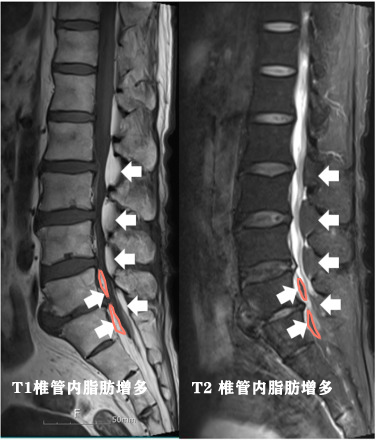

●脂肪瘤也会生长在脊柱内,这种情况以往核磁虽然有了体现,但是由于对这种疾病的认识过浅,往往容易被临床医生和操作医生所忽视,这种情况通常被成为:硬膜外脂肪瘤或特发性硬膜外脂肪增多症,胸椎发生比率较高,占60%,腰椎略少,占40%左右,这种疾病多见于常年使用激素人群和超重人群【2】。